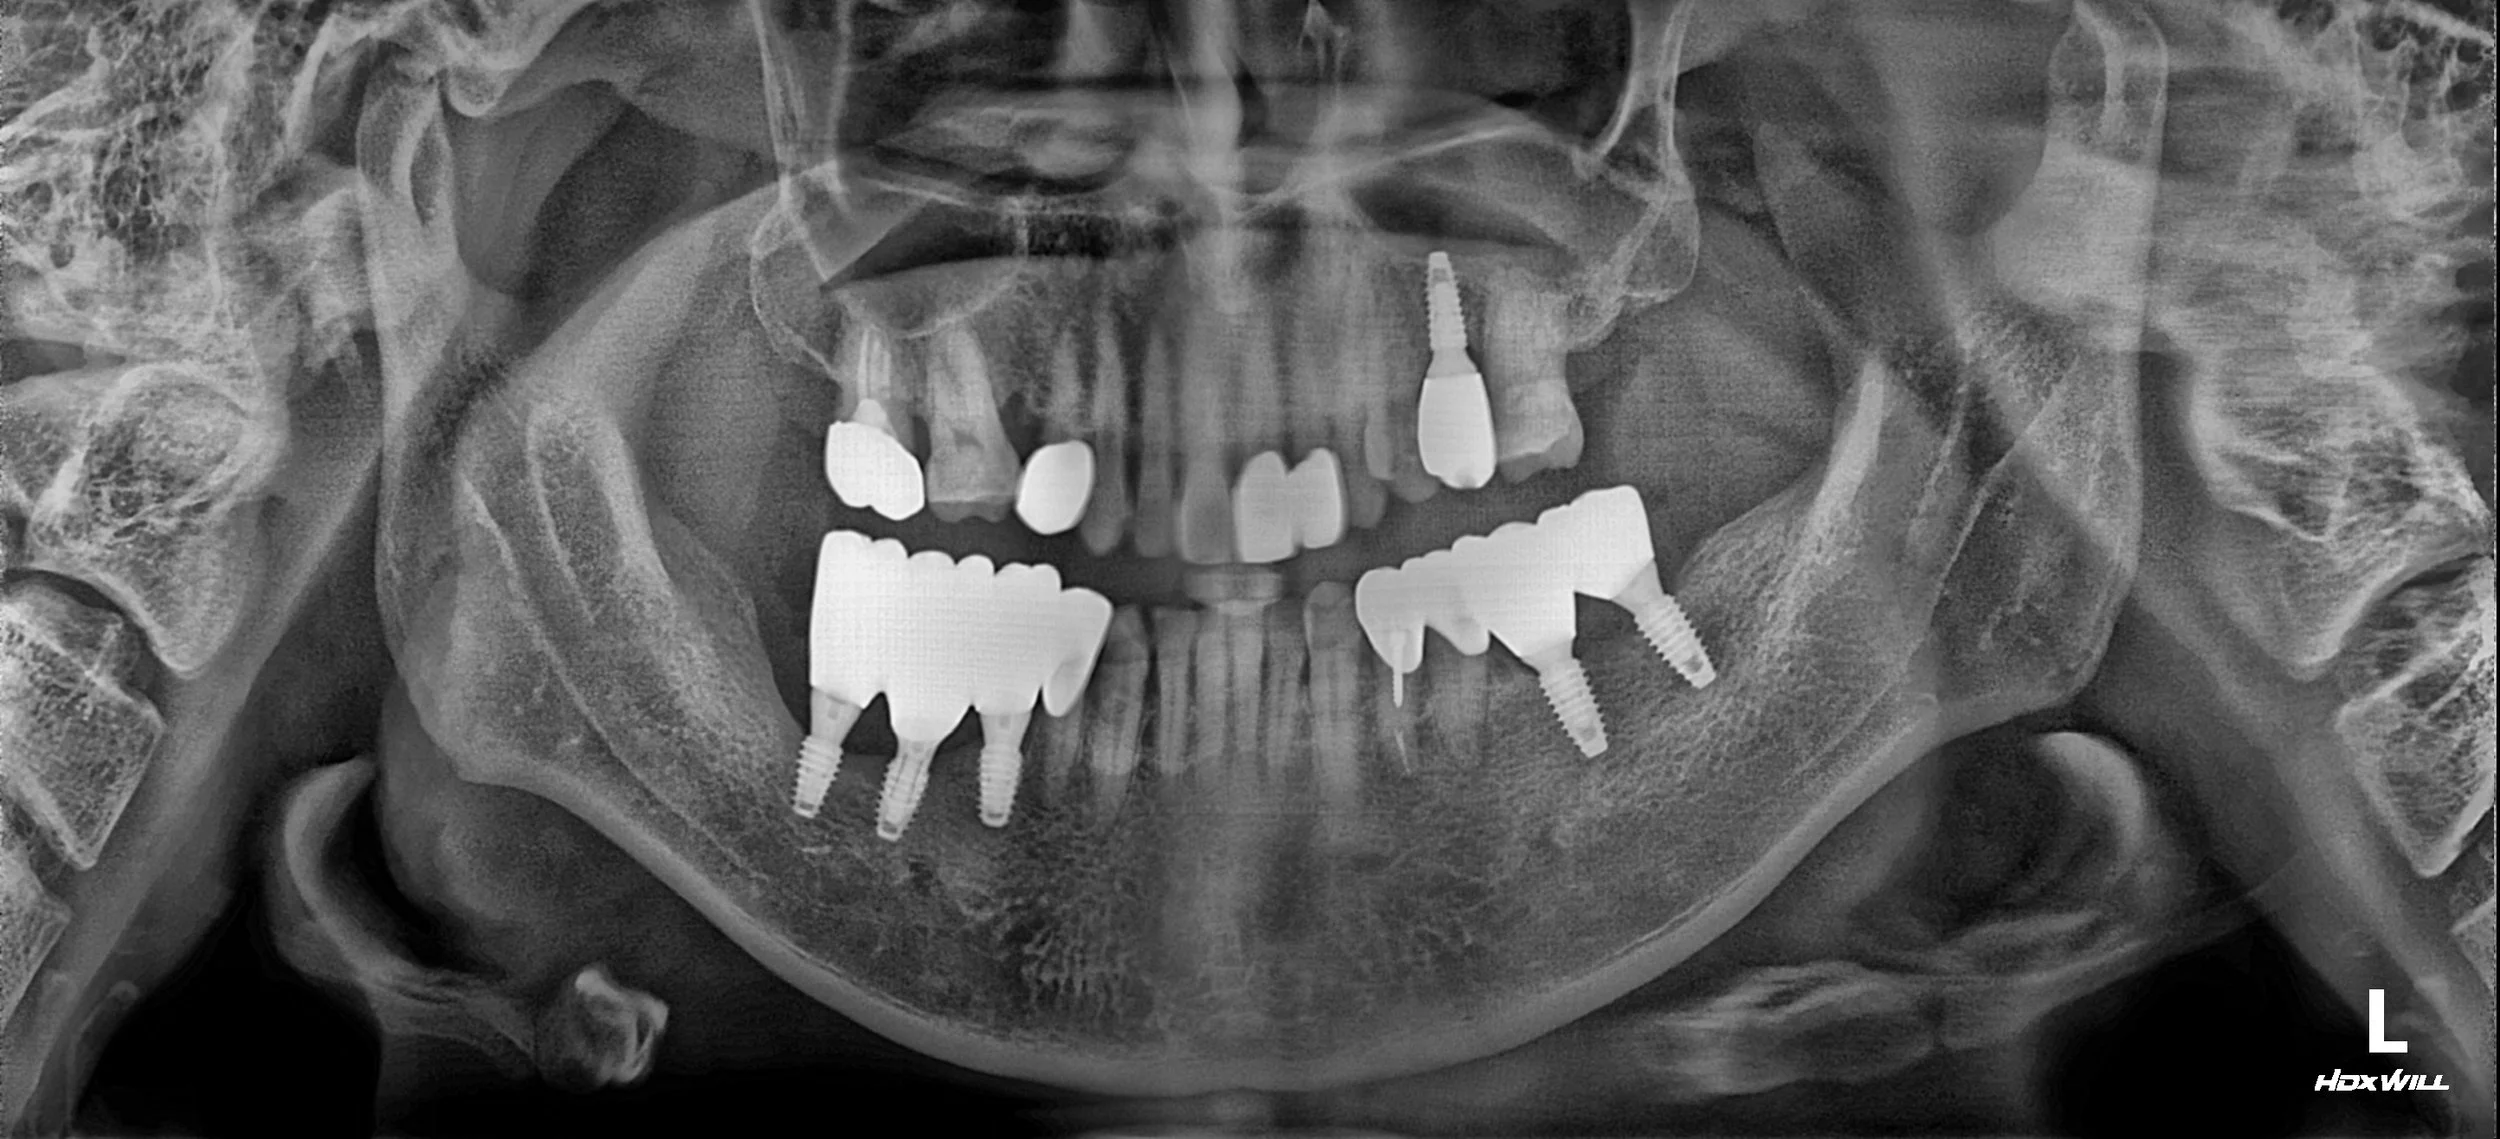

3. Prosthetic Revision & Functional Phase: Dental implants were strategically re-placed at the intended new VDO. This phase was meticulously planned to prevent future overloading and to harmonize with the new mandibular position. Comprehensive functional guidance was initiated using long-term provisional restorations. The patient was maintained in this stabilized temporary state for an extended period, allowing the neuromuscular system to fully adapt and ensuring the new bite position was repeatable and comfortable.

4. Final Prosthetic Phasing: Definitive zirconia implant-supported bridges were delivered. Particular attention was paid to creating a harmonious "emergence profile" for maintenance. The final occlusal scheme was designed to be "maintenance-friendly," ensuring easy access for hygiene, vital for patients with a history of severe failures.

The result is a transformative improvement, moving from the discomfort of iatrogenic failure and skeletal collapse to a stable, functional, and symmetrical fixed rehabilitation.